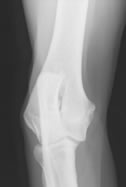

La valutazione ufficiale per il controllo della displasia del gomito prevedere che siano radiografati entrambi i gomiti, con cassetta radiografica posta sul tavolo a diretto contatto del gomito e senza l'impiego di griglie antidiffusione. Per la Centrale di Lettura della FSA sono richieste due proiezioni per ciascun gomito, una proiezione medio-laterale con il gomito mantenuto in flessione di circa 45°, senza pronazione né supinazione dell'estremità dell'arto, con sovrapposizione del profilo laterale e mediale del condilo omerale e con il fascio radiogeno centrato su di esso e delimitato all'articolazione.

La seconda proiezione richiesta è quella cranio-caudale obliqua con 15° circa di pronazione.